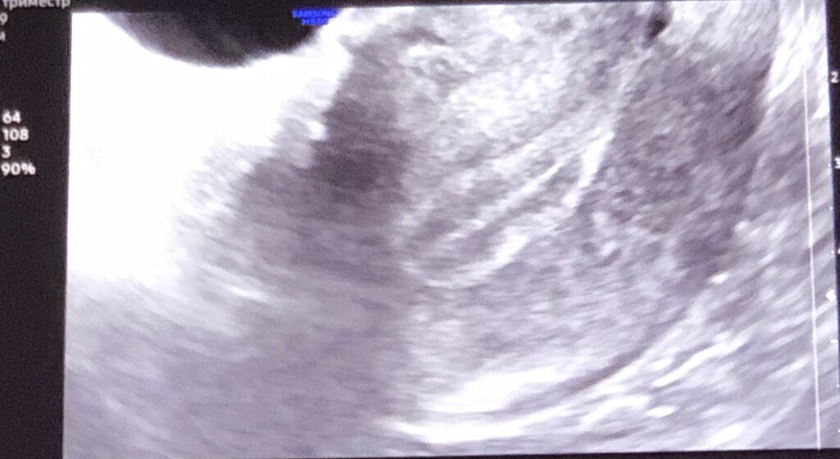

9 Дц эндометрий 10мм, повторная консультация в понедельник на 13 день цикла. Перевели с 3х разового на 2 раза в день прогинову и дивигель. Переживаю не будет ли гиперплазия, потому что подсадку будут делать 24 июля.

Прогестерон подключат и немного сдуется. У меня на 9 цд был 10.5, перенос на 18 дц делали на 11,8

Мне тоже перенос раньше делали, тк эндометрий раньше срока вырос. Он если сейчас уже 10, то куда там переносить так поздно, имплантации просто может не быть же